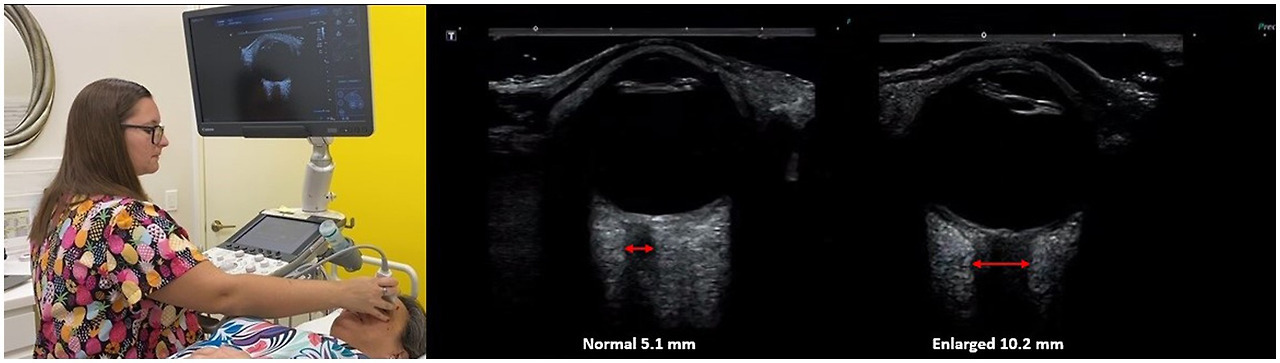

The optic nerve is well-suited for noninvasive eval‎uation of its diameter, as an ultrasound beam can travel unimpeded through the eyeball, which is mostly liquid. Historically, the optic nerve and its sheath diameter were noninvasively assessed by MRI and ophthalmoscopy, but transorbital ultrasound has recently emerged as a promising assessment tool (75). Ultrasound measurements of the optic nerve sheath diameter closely correlate with MRI measurements from in vivo and cadaver studies, and are reproducible (7677). Optic nerve sheath diameter has been shown to correlate with instantaneous assessments of ICP, including states of traumatic brain injury, and is even correlated with mortality (7881). Typically, optic nerve sheath diameters over 6.0 mm are considered abnormal, and one of the evidences for IBP (see Figure 8).

Figure 8

Figure 8. Ultrasound of eye to measure optic nerve sheath diameter, which is used as a marker for intracranial hypertension (increased brain pressure).